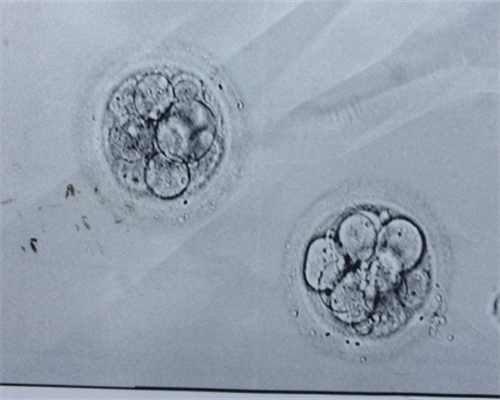

上海代怀生助孕公司拥有一支高水平的医疗团队和一流的助孕技术。其助孕生双胞胎的技术主要有两种:试管婴儿技术和胚胎分裂技术。试管婴儿技术是通过体外授精的方式使卵子与精子结合,培育成胚胎后再将其移植到代孕母亲体内,促进胚胎着床并发育成胎儿。而胚胎分裂技术则是通过人工手段将早期胚胎分裂成两个或多个,培育成多个胎儿后再将其移植到代孕母亲体内。